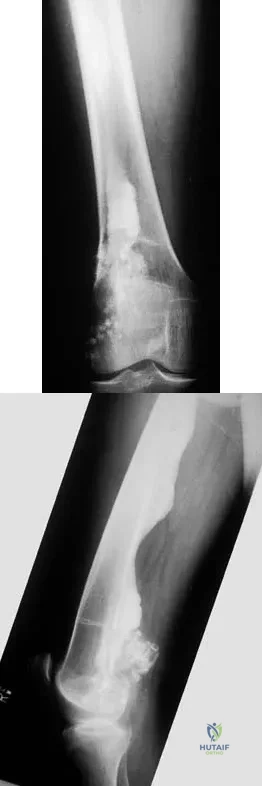

Figures 8a through 8c show the lateral radiograph and T1- and T2-weighted MRI scans of a 14-year-old soccer player who reports aching thigh pain. The next most appropriate step in management should consist of